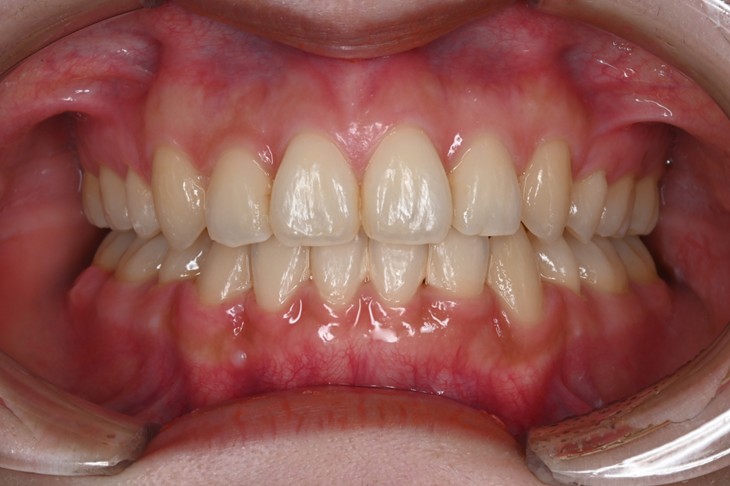

症例2:八重歯が気になる

| 患者様データ | 20代 女性 |

| 来院主訴 | 八重歯が気になる。 |

| 治療内容 | 八重歯を治すために上の親知らずを抜歯し、インビザラインにてマウスピース矯正を開始しました。かみ合わせを整えるためにゴムかけを行いました。 |

| 概算治療費 | 約85万円 |

| 治療期間 | 1年3ヶ月 |

| 通院回数 | 8回 |